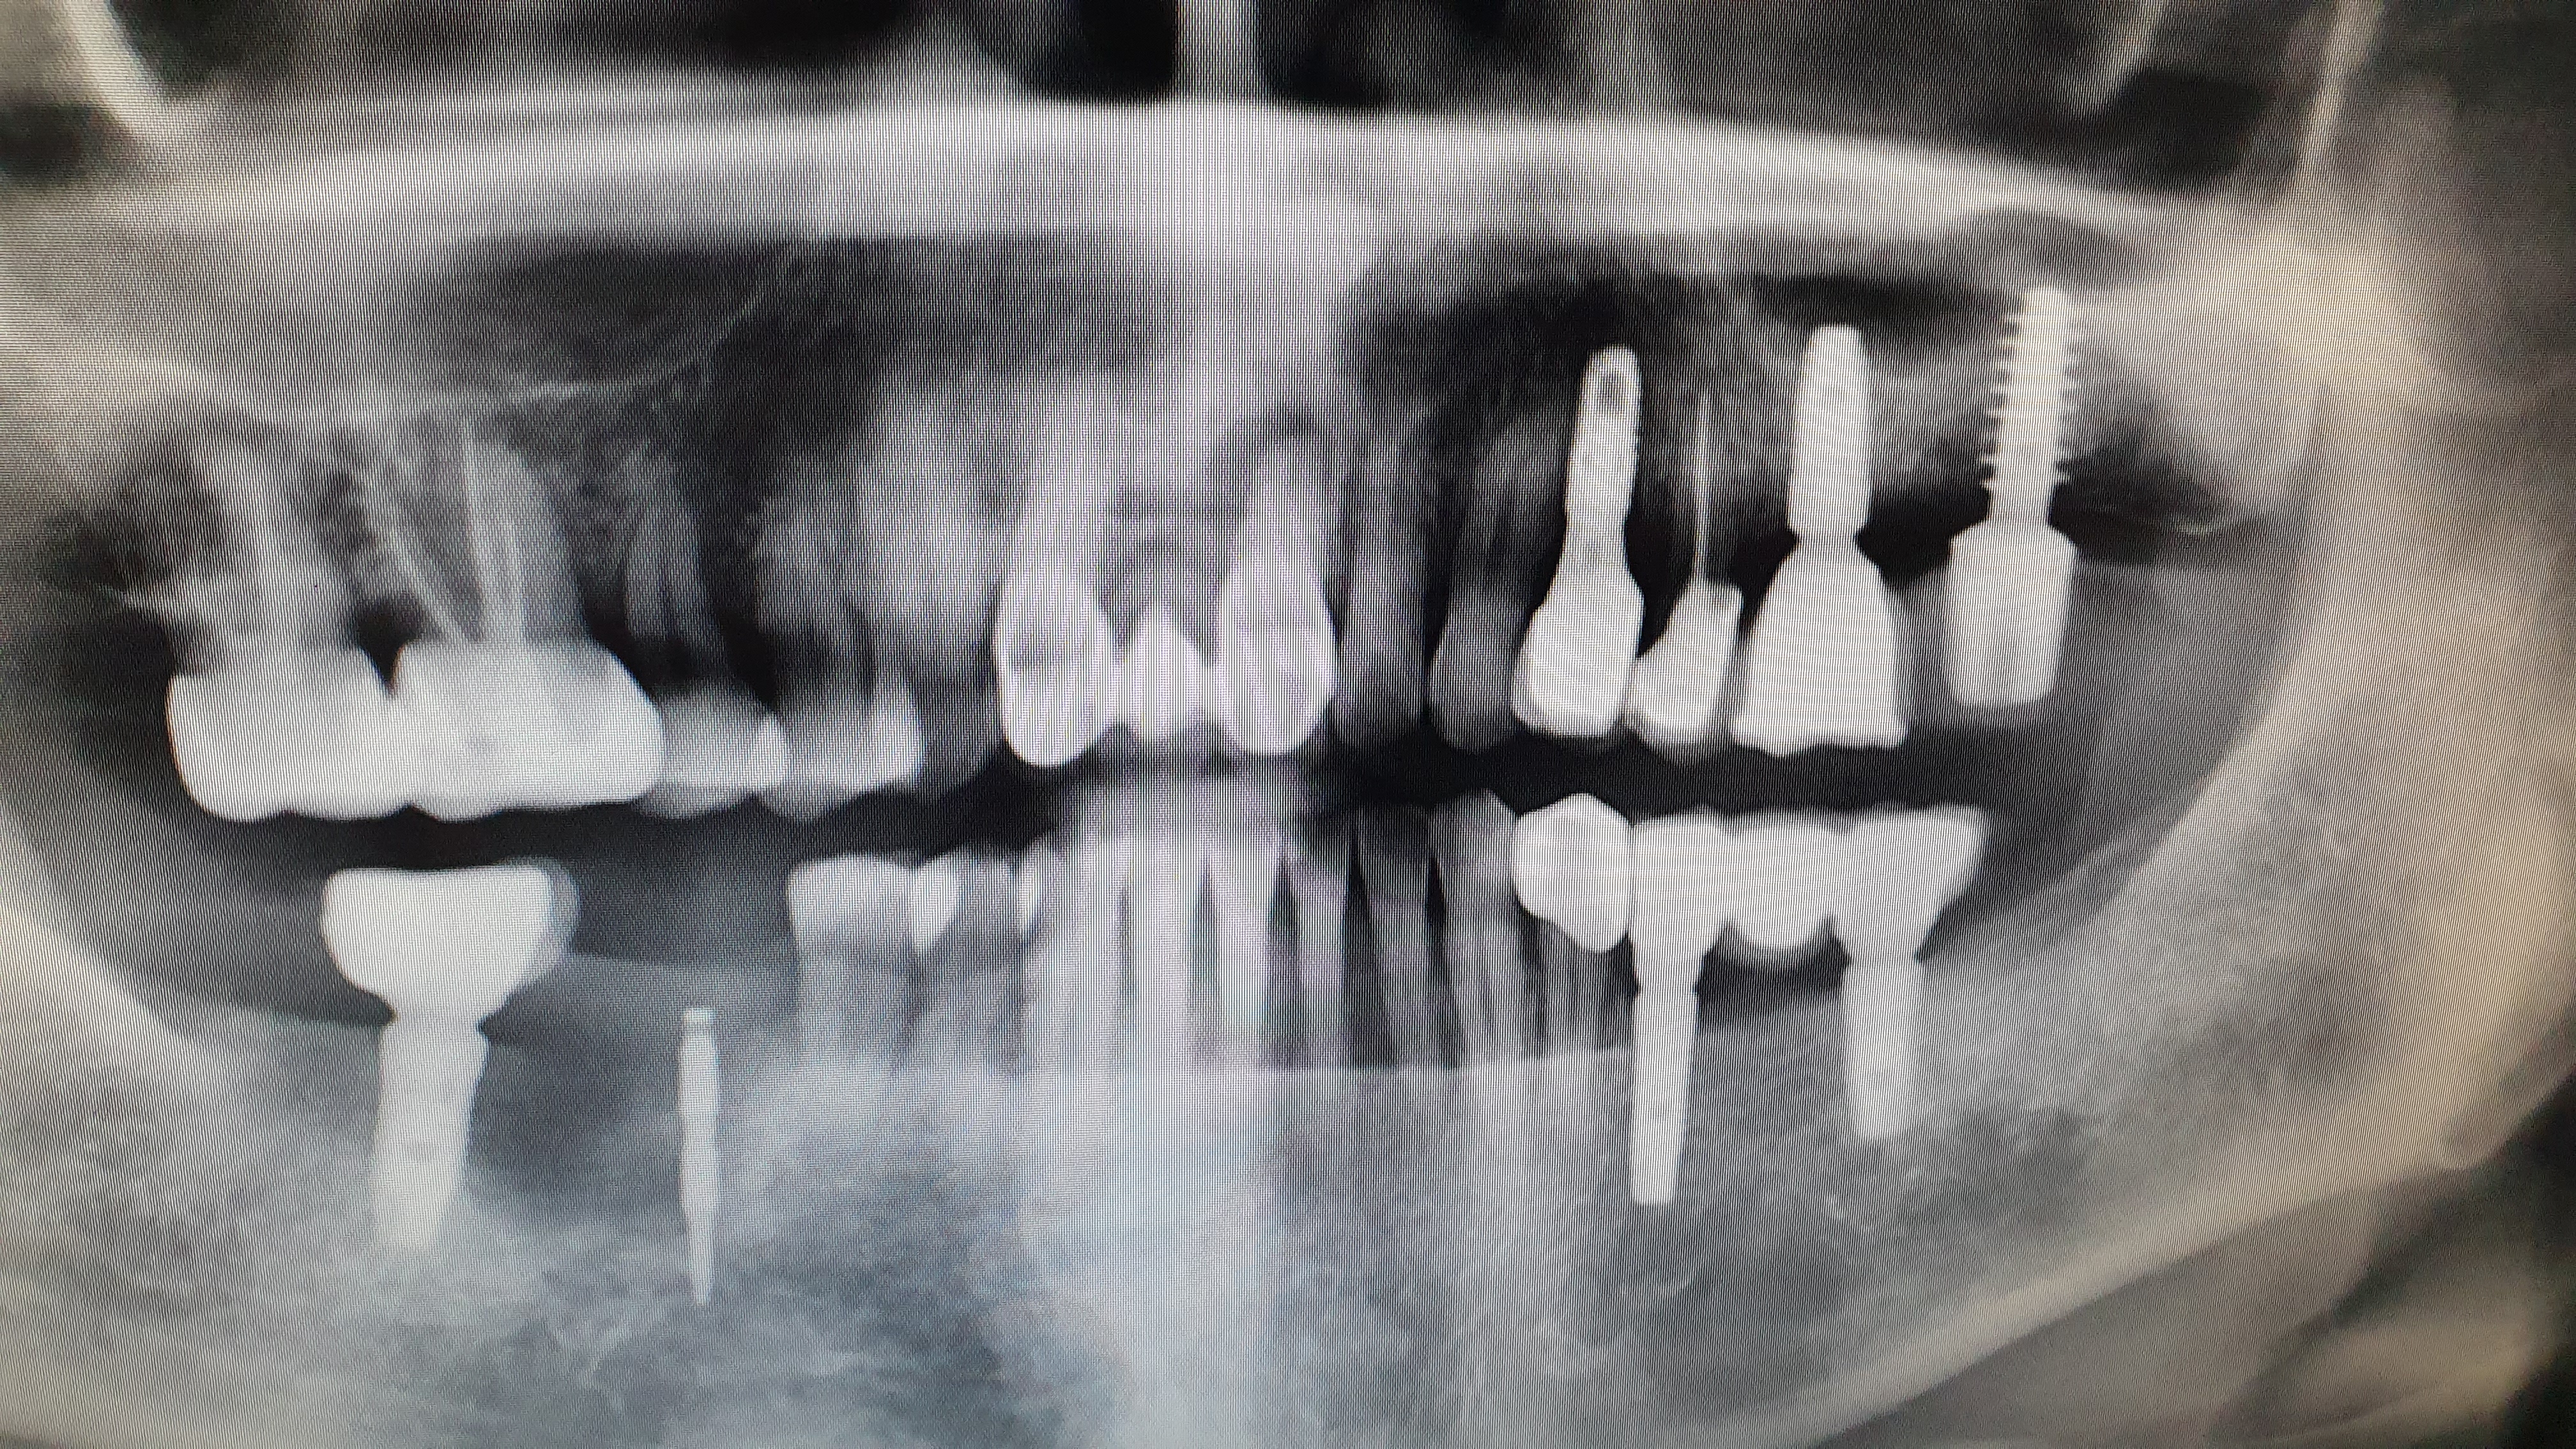

임플란트

일미치과